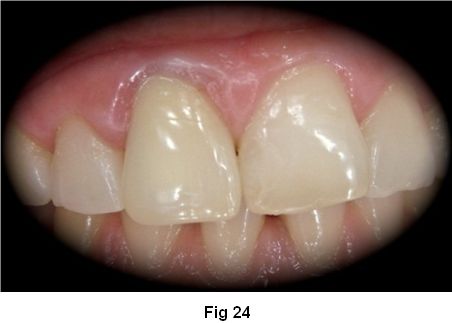

Control oclusal final. (Fig. 24)